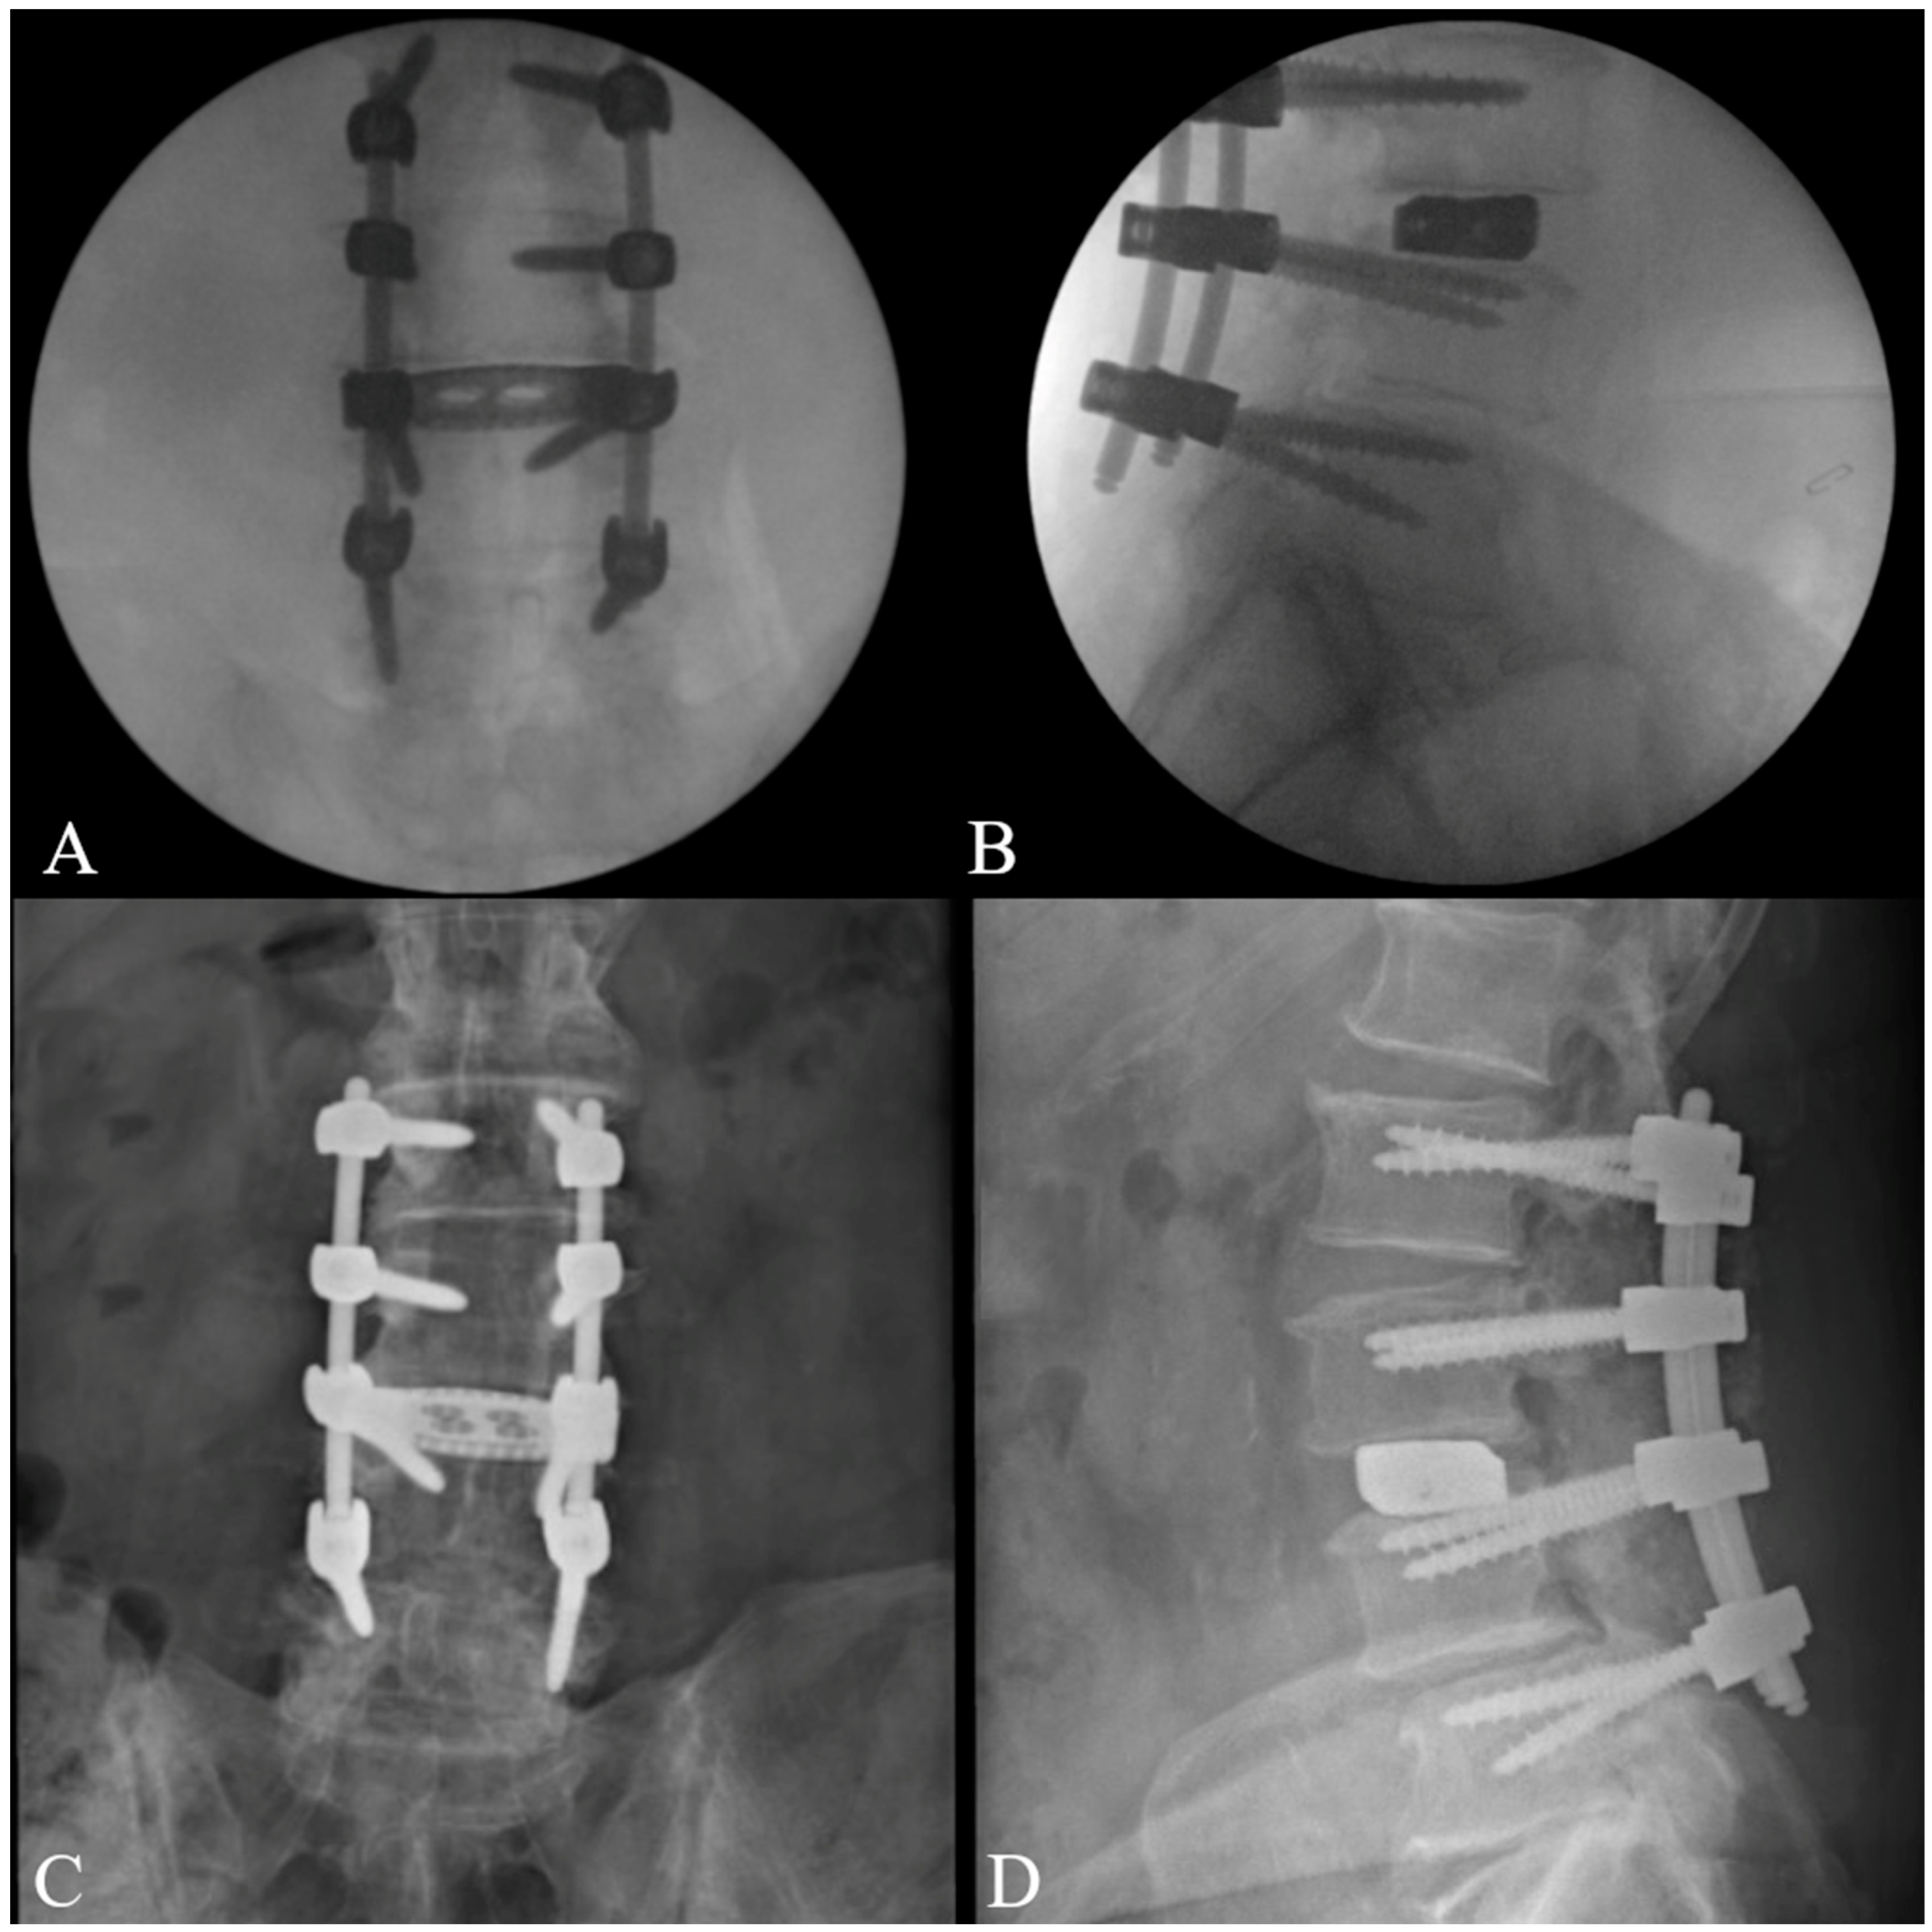

- North, R.Y.; Strong, M.J.; Yee, T.J.; Kashlan, O.N.; Oppenlander, M.E.; Park, P. Navigation and robotic-assisted single-position prone lateral lumbar interbody fusion: Technique, feasibility, safety, and case series. World Neurosurg. 2021, 152, 221–230.e1. [Google Scholar] [CrossRef] [PubMed]

- Huntsman, K.T.; Riggleman, J.R.; Ahrendtsen, L.A.; Ledonio, C.G. Navigated robot-guided pedicle screws placed successfully in single-position lateral lumbar interbody fusion. J. Robot Surg. 2020, 14, 643–647. [Google Scholar] [CrossRef] [PubMed]